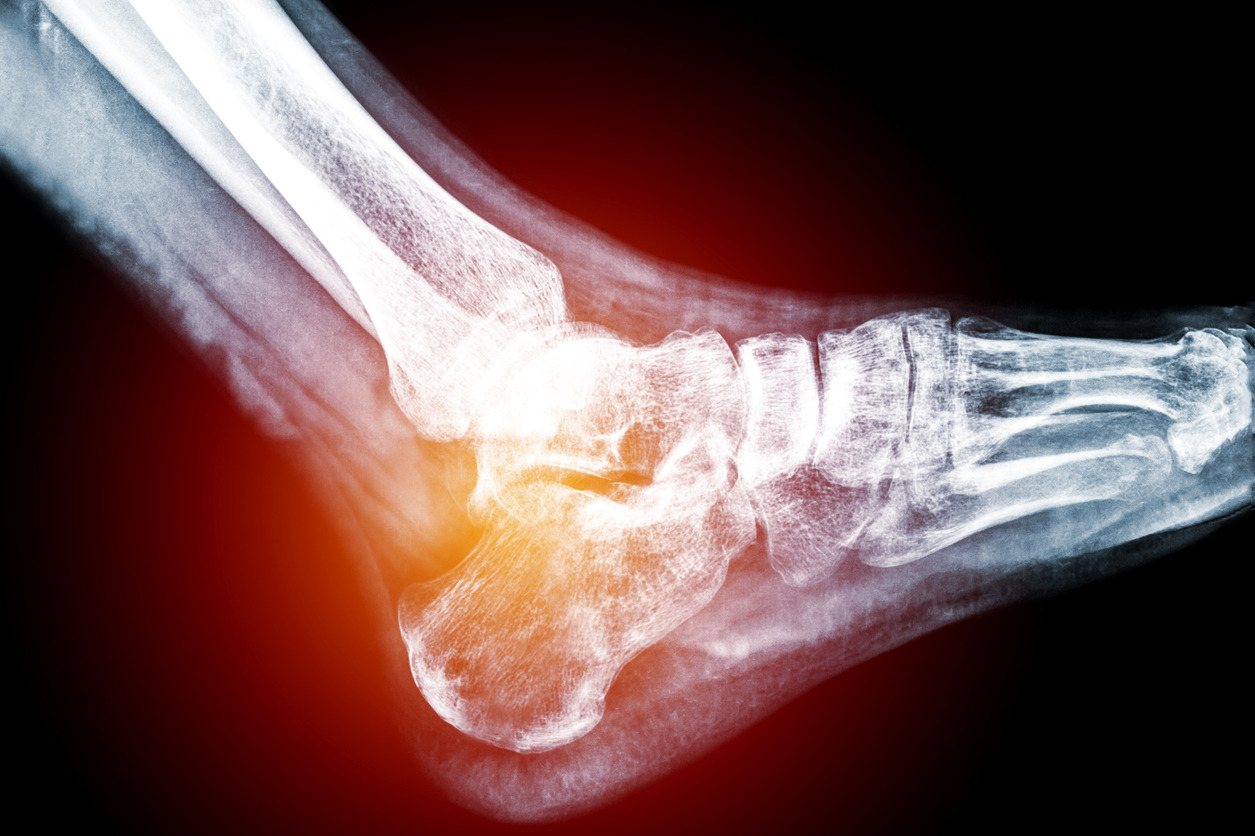

발목 부상 예방을 위한 십계명

운동 선수나 스포츠 동호인이라면 누구나 한 번쯤 경험하게 되는 발목 부상, 특히 동호인의 경우에는 대수롭지 않게 얼음 한 번 대주고 무심하게 넘어가는 경우가 대부분이지만 발목 부상은 그들의 생각처럼 만만한 상대가 아니다.

우리 몸에서 부상을 경험한 이후의 재발 가능성이 가장 높은 부위는 허벅지다, 그리고 다음으로 그 위험성이 큰 부위가 발목인데 둘은 손상부위에 차이에 있다. 허벅지 부상의 경우는 대개 허벅지 근육에 생기는 크고 작은 상처에 기인하는데, 발목의 경우 대부분의 부상 원인이 인대의 손상이라는 점이다.

염좌에 관한 이전 글에서 언급됐던 바와 같이 인대는 근육보다 상대적으로 긴 회복 시간을 필요로 하며, 부상 이전과 동일한 상태의 회복, 즉 완치가 불가능하다. 부상의 정도나 유형에 따라 차이는 있겠지만, 뼈와 뼈를 이어주고 관절을 유지시켜야 하는 인대의 특성상 구조적인 완벽성과 적절한 기능(장력)의 유지는 무엇보다 중요하다. 그런데 한 번 부상을 당하면 이 두 가지 모두를 잃게 된다.

발목 부상을 만만하게 보면 안 되는 이유가 여기에 있다.